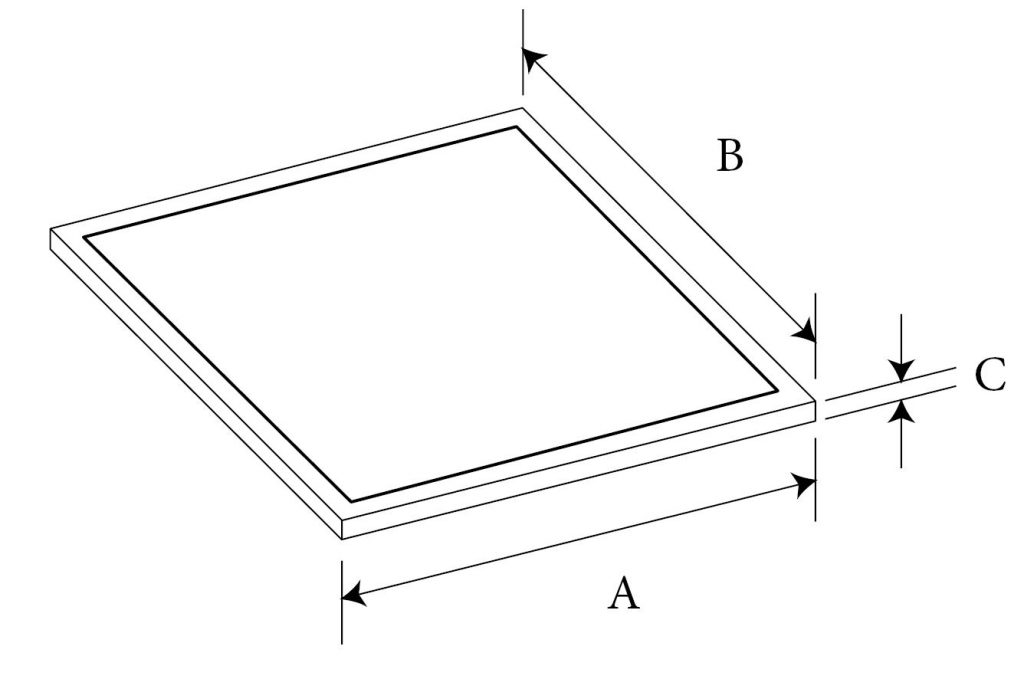

Membrane Sheet Dimensions

| Cat# | A | B | C |

|---|---|---|---|

| 4231 | 38mm | 50mm | 0.60mm |

| 4016 | 38mm | 50mm | 1.0mm |

| 4241 | 38mm | 50mm | 1.6mm |

| 4017 | 50mm | 76mm | 1.0mm |

| 4018 | 50mm | 76mm | 1.6mm |